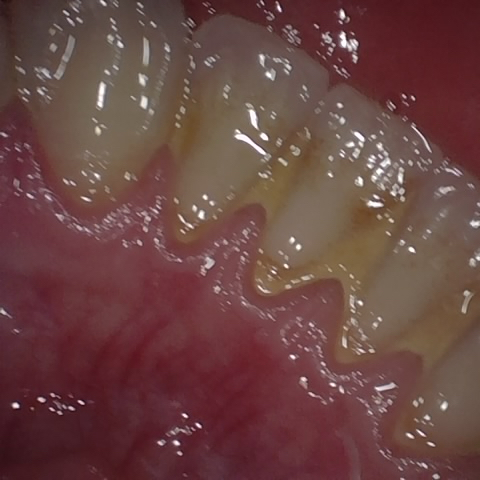

Annotated as "Good"